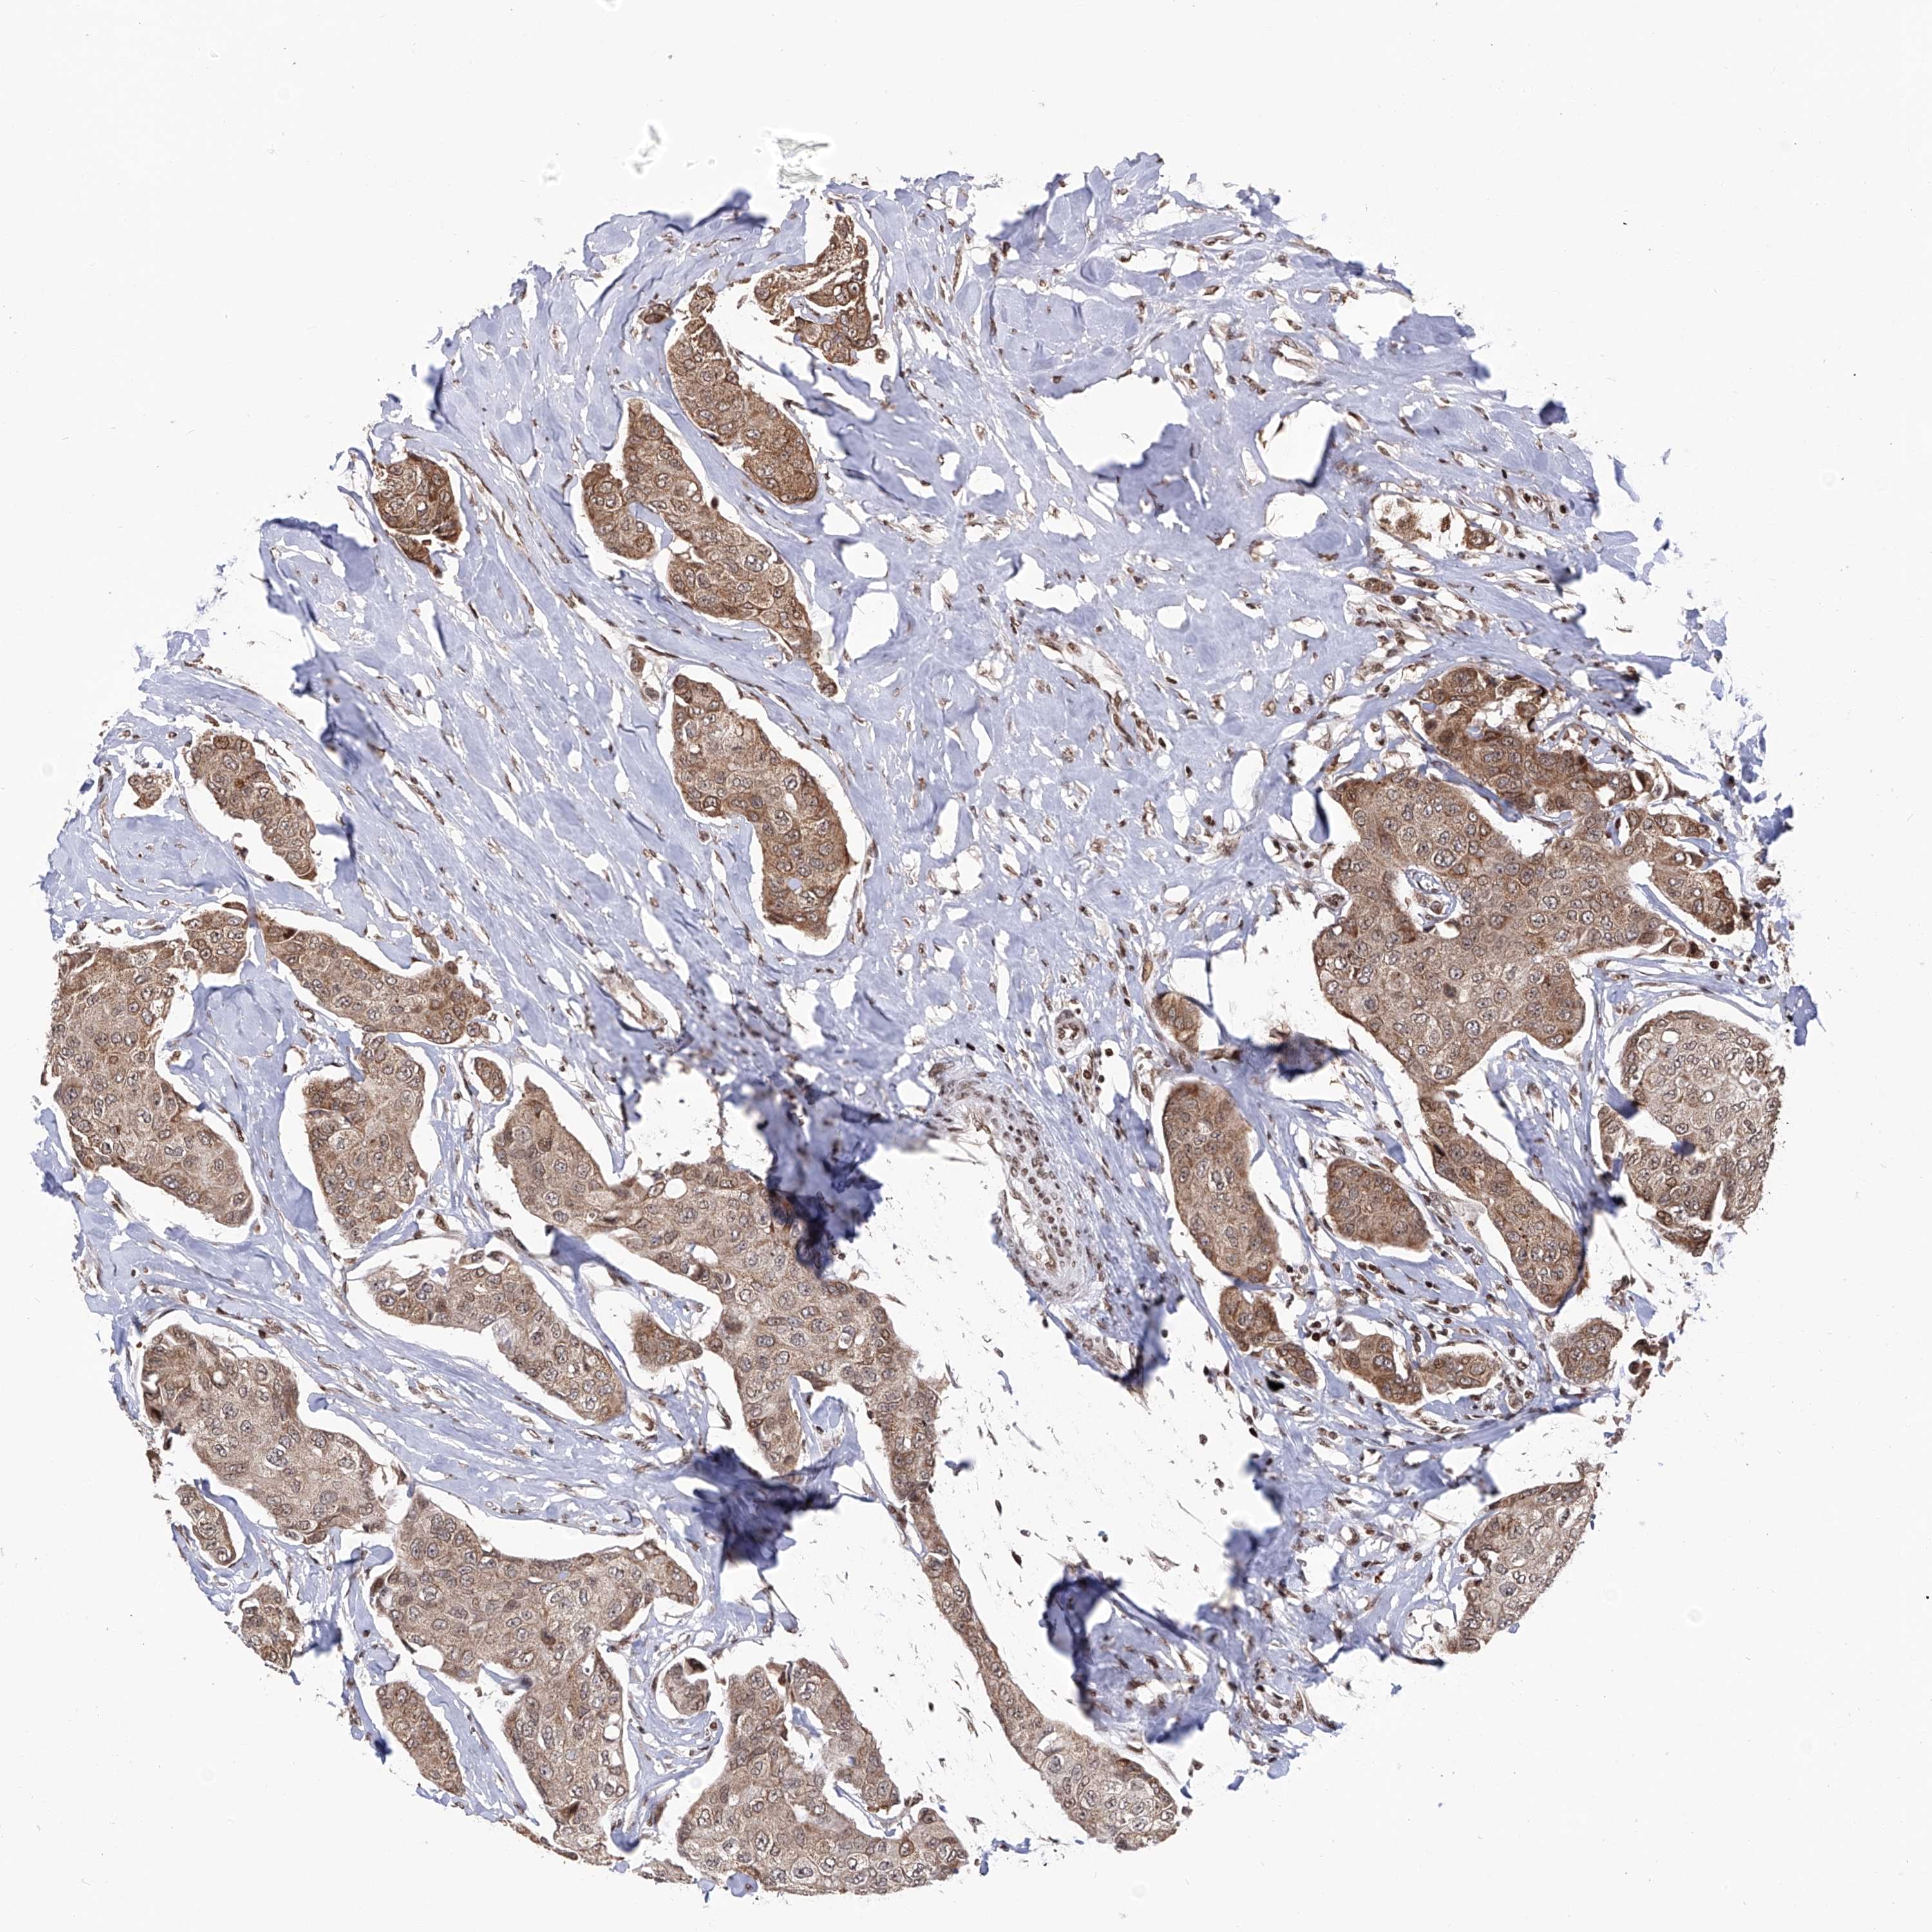

BRCA TCGA BRCA VALIDATION PROTEIN EXPRESSION

Breast cancer

Human cancer